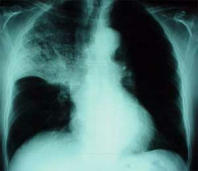

El grupo sanguíneo AB tiene - como el grupo sanguíneo A - un problema crónico de mucílago que provoca siempre enfermedades infecciosas: Sinusitis, bronquitis, pulmonía etc.

Ejemplo: Radiografía con pulmonía al lóbulo de pulmón superior con sombra en el centro  de la región derecha del pulmón.